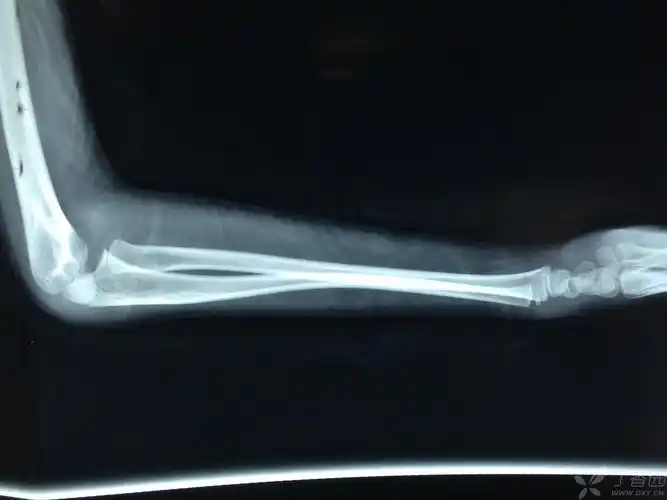

桡骨小头脱位,请求治疗方案 - 骨科 - 专业医生社区,医学,药学,生命科